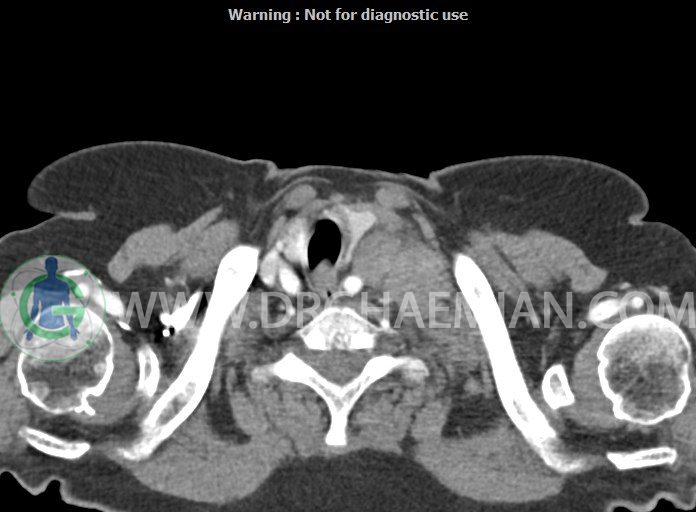

در سی تی اسکن اسپیرال از گردن با تزریق (مولتی دیدکتور 16 با مقاطع ظریف و بازسازی های ساژیتال و کرونال):

– تصویر توه های نسج نرمی oval shape متعدد با Enhancement تقریباً هوموژن، قرار گرفته در سمت چپ گردن، در لول غضروف کریکوئید با اثر فشاری شدید و compression ورید ژوگولار، با گسترش تحتانی به اینفراکلاویکولار چپ، به حداکثر ابعاد 28x50mm (با Enhancement مختصر هتروژن در این توده)

در درجه اول مطرح کننده لنفادنوپاتی متاستاتیک مطرح می باشد بالین، تومورهای منشأ گرفته از غلاف عصبی زنحیره سمپاتیک چپ گردنی، شبکه براکیال و لنفوم نیز در DDX قرار دارند. لذا نمونه برداری بافتی جهت بررسی بیشتر توصیه می شود.

– اسکولیوز مهره های سرویکال با تحدب به راست، احتمالاً در زمینه اثر فشاری توده های مذکور

مشهود است.